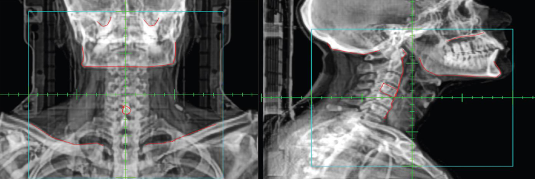

What type of image is this?

KV/KV